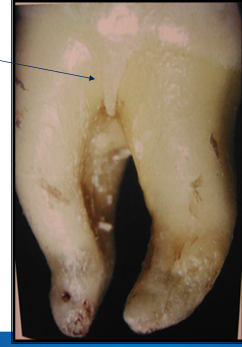

-cervical enamel projections

-won’t have attachment of CT with enamel

-projects into furcation area

-enamel pearl

-tends to involve furcation defects